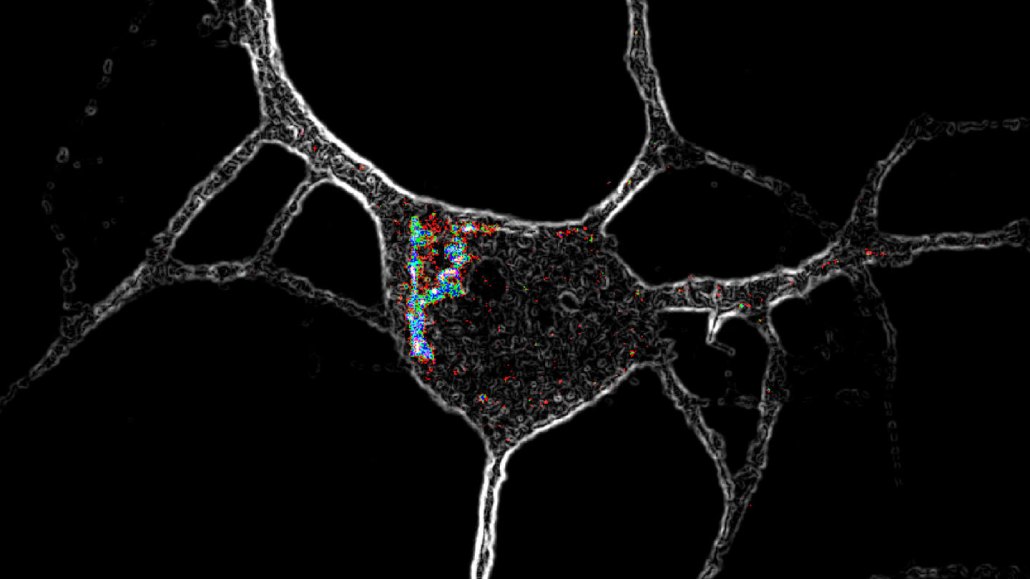

A microscope image of a nerve cell with colors highlighting special receptors.

Psychedelic chemical compounds like LSD activate special receptors (highlighted with colors in this microscope image) located inside nerve cells, causing the neurons to grow.